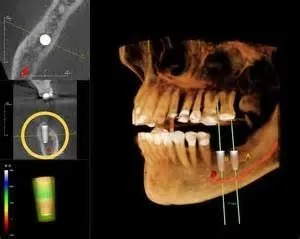

3D Imaging Technology provides three-dimensional imaging to the dental community, right in the practice office. The system offers active sagittal, coronal, and axial viewing and manipulation. It enhances diagnosis and treatment planning by providing more accurate imaging. Using the 3-D mapping tool, dental professionals can easily format and select desired slices for immediate viewing. Cone Beam imaging delivers quicker and easier image acquisition a typical scan takes only 20 seconds.

• More accurate treatment planning - confirm certain treatments are necessary.

• More predictable treatment outcomes.

The diagnostic images from the i-CAT scanner can be easily converted into a third party software (i.e. Simplant, Nobel guide, Dolphin, etc.) for pre-surgical evaluation and computer guided surgery. The doctor will receive a viewable animation to help him measure and analyze your case from every aspect. The data can also be used to fabricate your surgical guides.